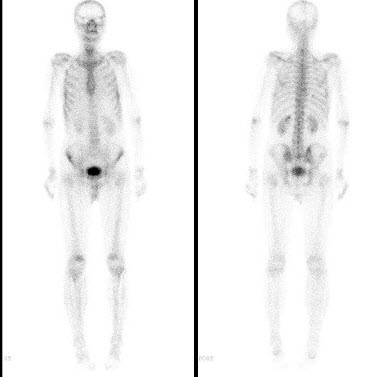

5、多项选择题

男,肝癌术后半年,诉胸背痛3个月,行Tc-MDP骨显像如图,可能的诊断是()

A.大致正常影像

B.胸12骨转移瘤

C.右侧第9后肋“冷区”

D.右侧第9后肋转移瘤

E.右侧第9后肋“甜面圈”征象

34、单项选择题

女性,53岁,乳腺癌术后3年,无明显不适,行99Tcm-MDP骨显像如图,最可能的诊断是()

A.大致正常的骨影像

B.超级骨影像,广泛骨转移

C.代谢性骨病

D.双肾功能严重受损

E.以上都不是